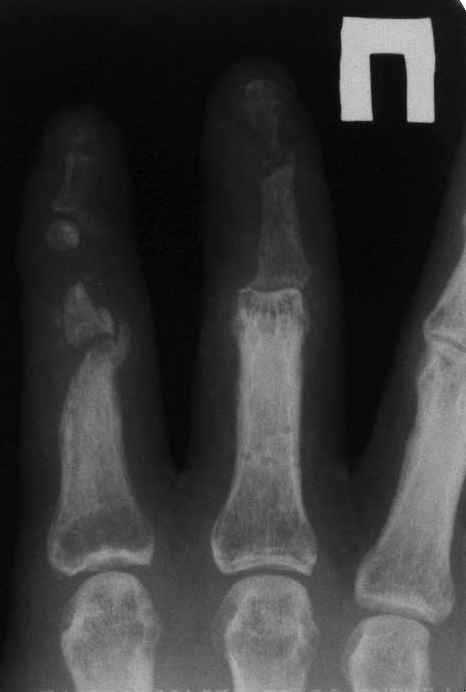

Уважаемые коллеги!На представленных снимках пальцы правой кисти мужчины 42 года через 3 месяца после травмы циркулярной пилой.

Качательные движения в проксимальном м/ф суставе 3 пальца. Нарушены все виды захвата, в которых принимают участие 2 и 3 пальцы. Кожные покровы с большими рубцами по тыльной и боковой поверхности пальцев. Ни магистральный кровоток, ни микроциркуляция специальными методами не оценивались. Косвенно о трофических нарушениях свидетельствует распространенный остеопороз дистальных фаланг и очаговый остеопороз основных фаланг и головок пястных костей, причиной которого возможно является и длительная иммобилизация в аппарате внешней фиксации. Чувствительных нарушений нет.

Планируем: 3 палец - открытый артродез дистального м/ф сустава с минимальной фиксацией спицей, тенолиз и разработка проксимального сустава (по этому пальцу в общем тактика ясна). 2 палец - обсуждается два варианта тактики:

1. Остеотомия основной фаланги, с последующей дистракцией в аппарате и удлинением последней до дистального м/ф сустава. Далее снова остеотомия - или неартроз, или эндопротез проксимального сустава, тенолиз. (Недостаток - будет потеряно время для восстановления функции сухожилий)

2. Костная пластика средней фаланги, одновременно тенолиз, артродез дистального м/ф сустава, разработка захватов. (Недостаток - опасаемся возможного некроза трансплантата вследствие ангиотрофических нарушений)Буду признателен за высказанные на форуме мнения по поводу пациента.